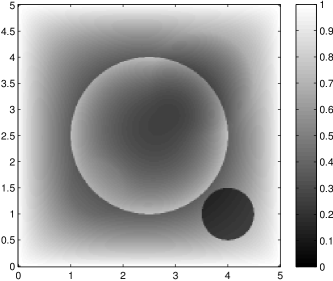

The data (see Figures 1 and 2) was generated in the diffusion model (1.2) using self-written (linear-basis) finite element code in MATLAB. For both examples, we took and used a uniform boundary condition . The simulated data were generated on a -grid and then down-sampled (by averaging) to to avoid inverse crime. After that, Gaussian noise with different intensities (standard deviations of and of the average signal value ) was added to the data.

The edge detector is used to detect jumps in the derivatives of the data up to second order (to obtain an initial estimate of the parameter jump set ). Since this process is highly sensitive with respect to noise, we varied the edge detection procedure subject to the amount of noise in the data. In the noise-free examples, we estimated the jumps of all three functions , that is, jumps of derivatives of up to second order. We restricted the jump estimation to for the low-noise examples (i.e., jumps of derivatives up to first order) and in the high-noise examples (only jumps in the data itself).

Reconstruction results and error profiles at different noise levels can be seen in Figures 3 and 4. In both examples, the noise-free reconstructions are very accurate and contain mostly smoothing error. In the low-noise reconstructions, due to the fact that more regularization is necessary, some of the parameter variation is underestimated. In the high-noise examples, most detail in is lost since a lot of regularization is required to get reasonable results. The fine detail in can, however, still be recovered very accurately in both examples.